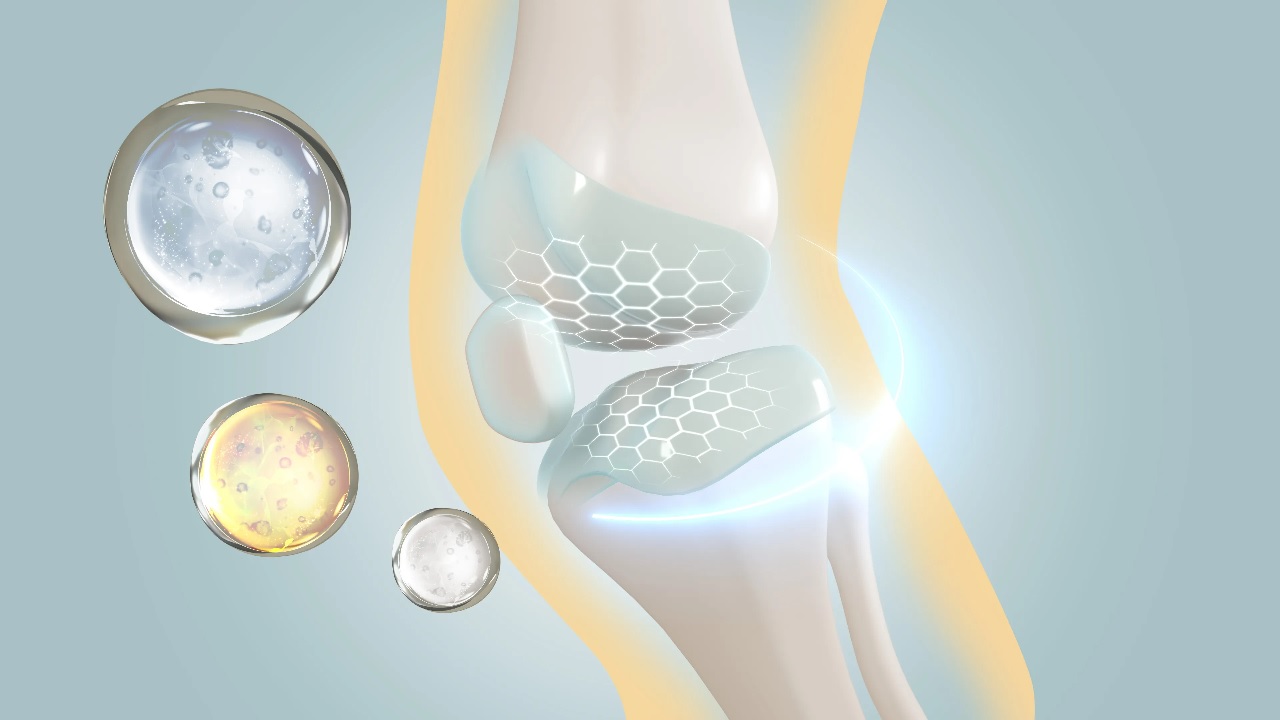

ابتكار علاجي يعيد بناء العظام والأنسجة دون تدخل جراحي.. فيديو

كشفت المخترعة والباحثة التقنية مياس آل حبتر عن ابتكار طبي جديد يهدف إلى إعادة بناء. […]